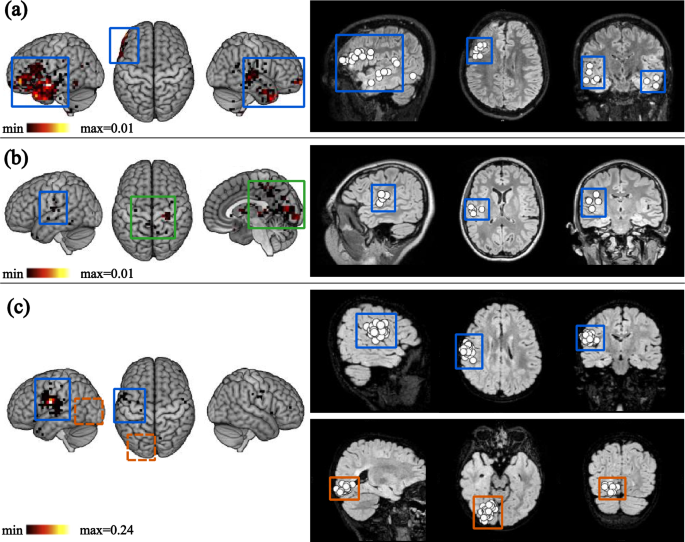

Figure 6 illustrates these results by comparing the density map of predicted IEDs (Fig. 6, left) and ECD localization of VDS-IEDs (Fig. 6, right) in three patients. Figure 6a is representative of the successful cases where STIED co-localizes IEDs with VDS-IEDs. Both approaches were consistent with multifocal independent irritative zones, with the most active being posterior to the left frontal lesion. Figure 6b illustrates a case of partial success. Clinical analysis reported few VDS-IEDs, which were accurately identified by the STIED model. Nonetheless, Rolandic spikes in the centrotemporal area and sleep-related events in the occipital areas were also wrongly predicted, likely indicative of physiological transients10,36. Figure 6c illustrates a case of mitigated success. Clinical assessment revealed two active, independent irritative zones located at the left opercular/periinsular and ventral occipital regions, which might be part of a common epileptogenic network, but STIED missed the ventral occipital cluster of VDS-IEDs. We conclude that, while STIED trained on FE patients learned IED features that generalize to all patients with RFE, other types of epileptiform activities were not recognized (such as polymorphic waveform), while some forms of physiological activity were falsely detected.

Localization of STIED predictions and VDS-IEDs in selected RFE patients. Left panel: Density maps of IEDs predicted by STIED, representing the fraction of IEDs predicted at each voxel. Color scales are adjusted to maximal fraction in patient. Right panel: ECD localization of VDS-IEDs. Each white dot indicates the dipole localization of one IED detected by visual analysis of MEG signals. (a) Successful example of coincident localization (blue squares). (b) Partially successful example where non-epileptiform events (green squares) are detected, such as Rolandic and sleep physiological transients. (c) Mitigated example where a cluster of VDS-IEDs is missed (orange squares) in the left-occipital part. All MRIs are in neurological convention.